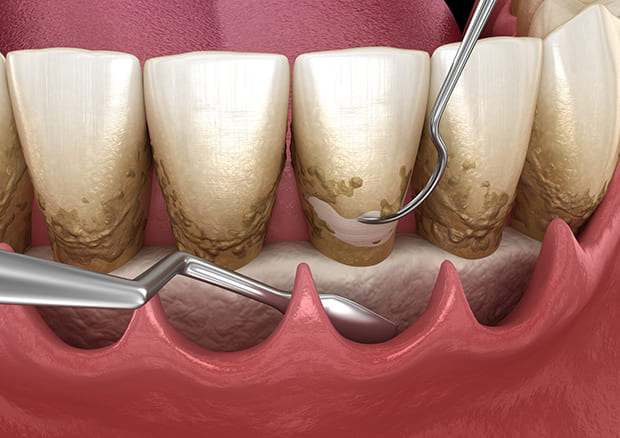

SRPとは、スケーリング+ルートプレーニングのことです。

このSRPは歯周病治療の1つで、専用の器具や、超音波の器具を用いて歯周ポケットの中、いわゆる歯茎の中の歯の根に隠れている部分の歯垢や歯石を取り除くことです。この歯石を歯肉の縁の下につく歯石ということから、縁下歯石(えんかしせき)といいます。

縁下歯石は、図のように黒っぽい色でセメント質と同一化し強固に付着しています。

当院のSRPは、特殊な医療機器を導入することで、迅速かつ合理的に縁下歯石を除去し、歯根表面を滑沢に仕上げることによって患者様の負担を減らし、治癒効果、歯周病再発予防効果に努めています。